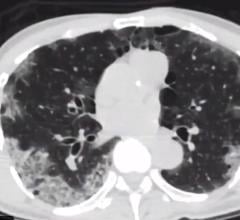

October 30, 2020 — Computed tomography angiogram (CTA) scans may offer fast and early detection of COVID-19 in acute ...

Todd Villines, M.D., FACC, FAHA, MSCCT, explains some of the discussion on CT used for COVID-19 patients at the Society ...